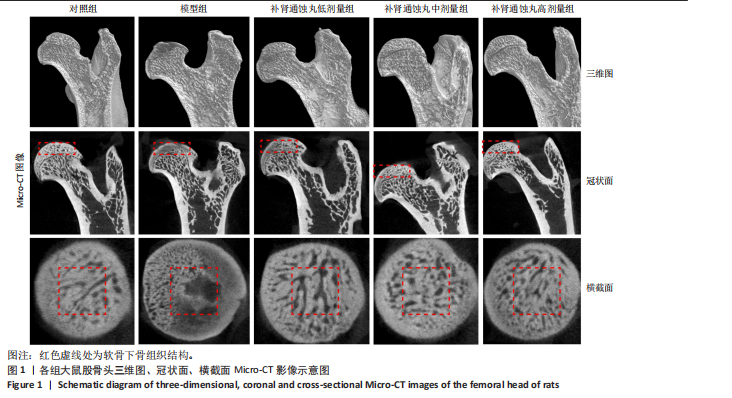

.1 实验动物数量分析 参加实验SD大鼠数量为50只,均进入结果分析。 2.2 Micro-CT检测结果 通过Micro-CT观察各组大鼠股骨头区域骨质变化,见图1。乙醇会导致大鼠股骨头软骨下骨骨量明显减少,骨小梁排列出现紊乱、稀疏等状况,而补肾通蚀丸能够改善上述情况,且呈现一定的剂量效应。模型组骨小梁厚度、骨小梁数目、骨体积分数、骨密度较对照组显著降低(P < 0.01),模型组骨小梁间隙较对照组则显著升高(P < 0.01)。经过不同剂量补肾通蚀丸干预后,各项指标均出现不同程度的逆向改变;其中,与模型组比较,补肾通蚀丸高剂量组骨小梁厚度、骨小梁数目、骨体积分数、骨密度均显著升高(P < 0.05),骨小梁间隙则显著降低(P < 0.05);与模型组比较,补肾通蚀丸中剂量组骨体积分数、骨密度显著升高(P < 0.05),骨小梁间隙则显著降低(P < 0.05);而补肾通蚀丸低剂量组仅在骨小梁间隙指标上较模型组显著降低(P < 0.05),见图2。 2.3 苏木精-伊红染色结果 与对照组比较,模型组大鼠股骨头出现核固缩现象,多见脂肪空泡,部分骨小梁出现断裂、变细;补肾通蚀丸低、中、高剂量组骨细胞核固缩和脂肪空泡较模型组有所减少;在整体结构方面,补肾通蚀丸低剂量组骨小梁变细现象较模型组未见明显改善,但断裂情况有所改善;而补肾通蚀丸中、高剂量组骨小梁断裂、变细情况较模型组均明显改善,见图3;在空骨陷窝率方面,模型组较对照组显著增高(P < 0.01);补肾通蚀丸中、高剂量组较模型组有所降低(P < 0.05),见图3。 2.4 免疫组化染色结果 与对照组比较,模型组NLRP3、Caspase-1、消皮素D蛋白表达明显增强,而Runt相关转录因子2、骨钙素、Ⅰ型胶原蛋白表达显著降低(P < 0.01);与模型组比较,补肾通蚀丸中、高剂量组能够显著降低NLRP3、Caspase-1、消皮素D蛋白表达,且促进Runt相关转录因子2、骨钙素、Ⅰ型胶原蛋白表达(P < 0.05),而补肾通蚀丸低剂量组骨钙素、Ⅰ型胶原蛋白表达有所上调(P < 0.05),其余指标则无明显差异(P > 0.05),见图4,5。 2.5 ELISA检测结果 与对照组比较,模型组大鼠血清中白细胞介素18和白细胞介素1β水平显著增高(P < 0.01);与模型组比较,补肾通蚀丸各剂量组大鼠血清中白细胞介素18和白细胞介素1β水平均显著降低(P < 0.01),且以一定剂量依赖方式递减,见图6。 2.6 Western blot检测结果 与对照组比较,模型组大鼠股骨头组织中NLRP3、cleaved-Caspase-1、Caspase-1、消皮素D、消皮"